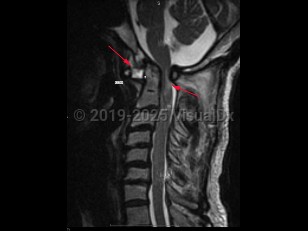

Atlantoaxial instability (AAI) is defined as excessive motion between the first cervical vertebra, the atlas, and the second cervical vertebra, the axis. The atlantoaxial segment is an anatomically complex section of the spinal column, composed of unique bones, articulations, and ligaments, with critical neurovascular structures intimately involved. The atlantoaxial segment is responsible for significant motion in the spine, and, in fact, is responsible for over half the possible axial rotation of the cervical spine. Disruptions of any of the ligaments or articular processes that afford nonpathologic motion of the atlantoaxial segment may result in instability of the complex. AAI can occur due to trauma, rheumatoid arthritis, congenital abnormalities (including up to 20% of Down syndrome patients), degenerative changes, head and neck infections, neoplasms, or iatrogenic etiologies. Most commonly, AAI results from compromise of the ligamentous complex; however, fractures or destructive processes affecting the osseous elements may also result in AAI.

AAI can occur in 3 directions: rotation, flexion-extension, and distraction leading to excessive displacement, which can result in subluxation or even dislocation.

Anterior atlantoaxial subluxations are more common in adults and result from any of the pathologies listed above. Anterior subluxations result in neurologic deficits or death in one-third of patients. Patients with rheumatoid arthritis (RA) are at most risk for dislocation in the anteroposterior (AP) plane but can develop rotational AAI as well.